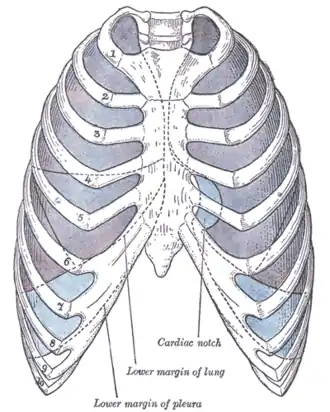

The costodiaphragmatic recess, also called the costophrenic recess or phrenicocostal sinus,[1] is the posterolateral fringe of the pleural space, a potential space around the lung inside the pleural cavity. It is located at the acutely angled junction ("reflection") between the costal and diaphragmatic parietal pleurae, and is interpreted two-dimensionally on plain X-rays as the costophrenic angle. It measures approximately 5 cm (2.0 in) vertically and extends from the eighth to the tenth rib along the mid-axillary line.

In anatomy, the costophrenic angles are the places where the diaphragm (-phrenic) meets the ribs (costo-).

Each costophrenic angle can normally be seen as on chest x-ray as a sharply-pointed, downward indentation (dark) between each hemi-diaphragm (white) and the adjacent chest wall (white). A small portion of each lung normally reaches into the costophrenic angle. The normal angle usually measures thirty degrees.